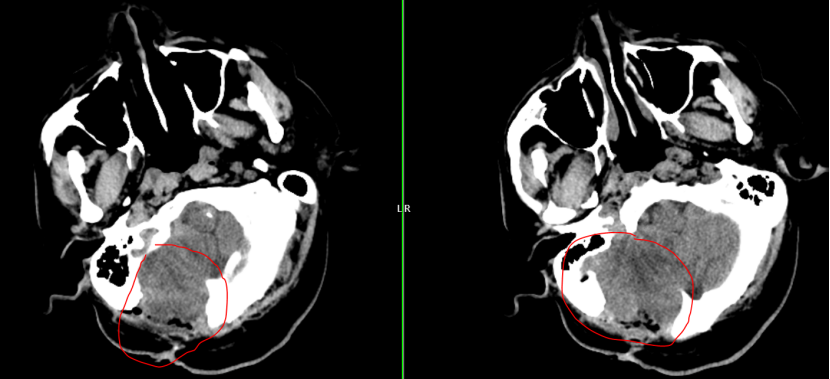

2024年初:肿瘤出现了第一次“跨界”转移。朱先生因剧烈头痛头晕入院,检查发现癌细胞由血液转移右侧小脑半球,约39mm×35mm大小,周焱峰主任带领团队为其行 显微镜下右侧小脑巨大转移瘤切除术,手术顺利完成。术后配合放化疗,病情稳定。

2025年8月:患者头晕、呕吐症状加剧,复查头颅MRI显示右侧小脑半球恶性肿瘤复发,约45mm×35mm大小,周围水肿严重,同时患者合并高血压和糖尿病,治疗难度加大。

d84a2104a197187fe3fdfdee7777982f.png edfb3326afa1a39fecbbd896f71cd773.png

此次手术面临诸多挑战:手术区域有疤痕和粘连,结构不清,容易出血;肿瘤位于小脑,紧邻脑干,手术中必须保护好神经功能;首次手术后部分枕骨缺失,脑组织生理结构已有改变,对手术入路设计和术中脑组织保护提出了更高要求。

面对如此棘手的局面,周焱峰主任带领团队进行详尽的术前讨论,研读MRI影像,模拟手术入路,为其量身制定手术预案和应急预案。